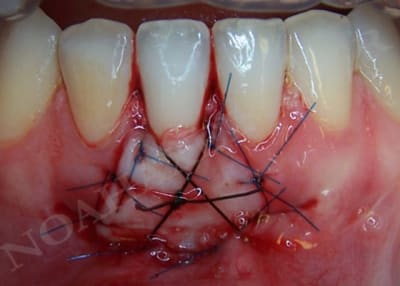

Par contre dans le cas suivant le but était de recréer un environnement gingival compatible avec une bonne santé parodontale :

Greffe gingivale libre slhq1i - Eugenol

Cicatrisation sondage xk347o - Eugenol